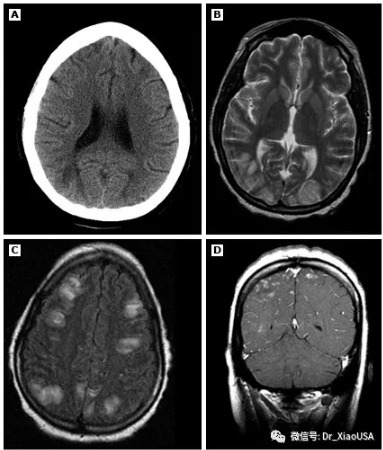

Question:The diagnosis of hypertensive encephalopathy in the ED usually relies on the exclusion of alternative causes of altered mentation. What level of Blood Pressure is required to develop hypertensive encephalopathy?

在急诊科诊断高血压性脑病通常依赖于排除导致神智改变的其他原因。

那么,多高的血压才能出现高血压脑病?